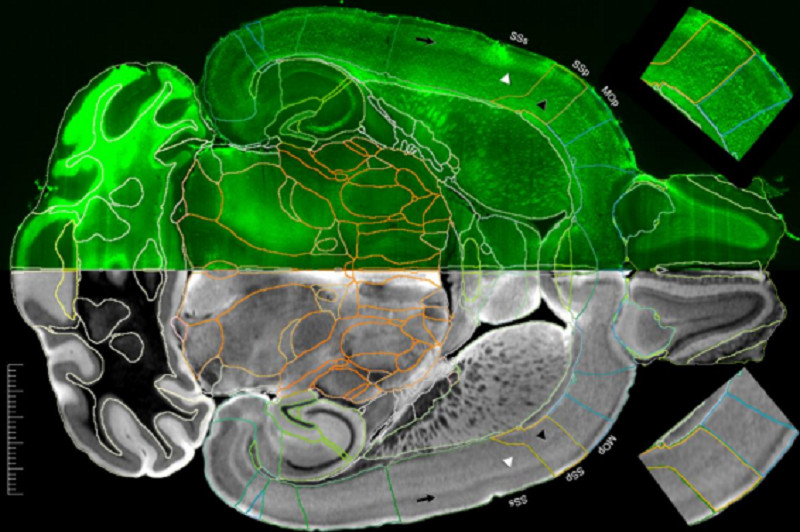

Американские ученые заявили, что смогли получить самые подробные изображения МРТ мозга мыши за всю историю исследований. По их словам, разрешение этих изображений в 27 тысяч раз превышает качество предыдущих.

Группа ученых из разных американских университетов опубликовала в журнале Proceedings of the National Academy of Sciences результаты исследования и рассказали, как добились самого подробного МРТ-изображения мозга грызунов за всю историю наблюдений.